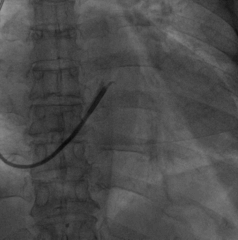

再次尝试后侧静脉,改用Sprinter Legend2.5X15mm预扩球囊扩张,可见明显腊肠样狭窄,给予28atm时方可见完全扩张

电极仍然无法通过,造影发现狭窄依然存在

尝试鞘中鞘试图通过狭窄处,但电极仍然无法通过

尝试Quantum Maverick3.0X12mm后扩球囊进行扩张

电极依然无法通过狭窄处,放弃手术?

尝试抓捕器在右房抓捕runthough导丝成功,并进行牵拉

非常幸运,通过抓捕器的牵引力,电极顺利通过狭窄处,确定电极固定牢靠,抓捕器释放导丝并撤出,初步测试左室阈值满意,没有PNS。